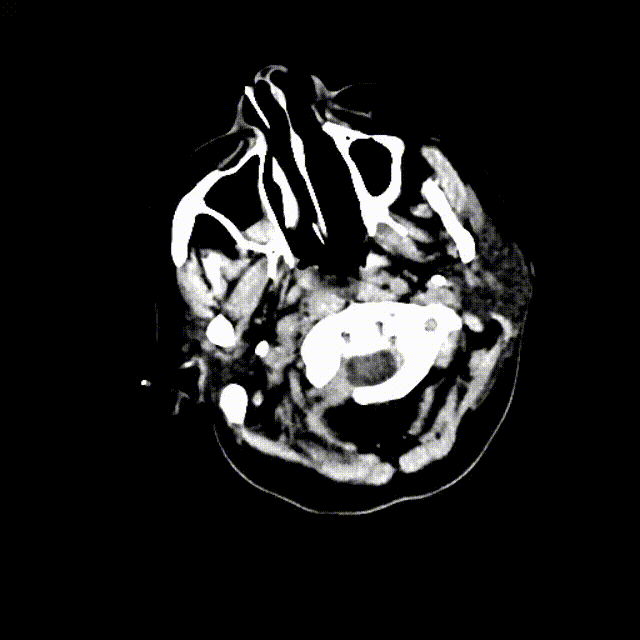

图6. A为患者术后1天CT平扫;B为患者术后5天CT平扫;C为患者术后5天DWI影像,可见大脑皮层、小脑、脑干散在新发梗塞灶。